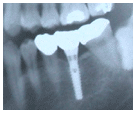

1) 이가 없는 잇몸뼈에 티타늄으로 된 인공치아, 즉 임플란트를

심습니다. 이는 보통 치과에서 일반적으로 하는 국소마취정도로 충분한 수술입니다.

2) 심겨진 임플란트가 잇몸뼈와 단단히 붙는 것을 확인하기

위해 몇 개월 정도의 기간을 기다립니다. 이때는 입안을 깨끗이 하는 것에 유의 하시면

되고 치과에 자주 내원할 필요는 없습니다. |

3) 임플란트가 뼈와 단단히 붙었다고 확인되면 뼈 속에

들어가 있는 임플란트를 이용하여 인공치아를 만들어 줍니다. |